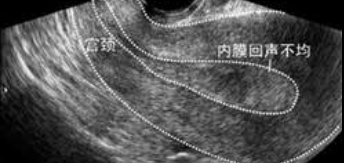

做B超检查时总会遇到内膜回声不均匀的情况,面临这一情况大多数姑娘都会又懵又慌,总担心会影响到怀孕,因此来听听李湘元医生介绍了内膜回声不均怎么办事吧!

做B超检查时,如果发现内膜回声不均匀,往往考虑是子宫粘膜下肌瘤,而且出现这种情况还可能导致月经失调,因此姐妹们还需要完善其他检查以明确病因。

但如果内膜回声不均持续存在,那可能就是以下几种情况:子宫内膜增生、宫腔粘连、子宫内膜息肉、粘膜下肌瘤、子宫内膜癌等。这需要结合患者的病史、查体和超声的具体显像判断,明确诊断需要宫腔镜检查+病理检查。